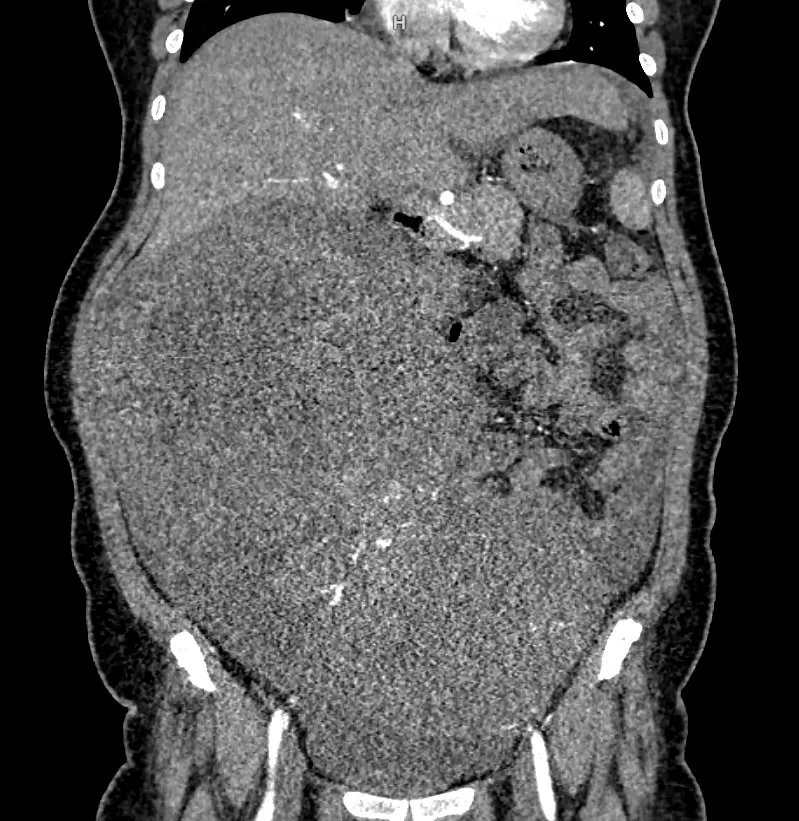

Kết quả chụp cắt lớp vi tính cho thấy khối u lan tỏa vùng hạ sườn phải, quanh rốn và hạ vị với kích thước lên tới 22,7 x 29 cm, bờ không đều. Khối u tiếp xúc và chèn ép nhiều cơ quan như gan, túi mật, thận phải, tụy, đồng thời dính với đáy tử cung. Ngoài ra, bệnh nhân còn có tình trạng dịch ổ bụng nhiều và tràn dịch màng phổi hai bên.

Hình ảnh phim chụp cho thấy khối u chiếm toàn bộ ổ bụng, đè đẩy các nội tạng xung quanh